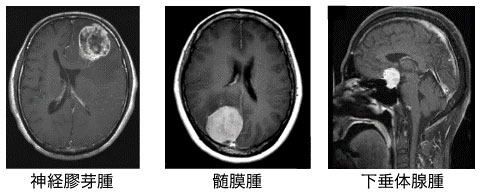

脳腫瘍は、神経膠腫、髄膜腫、下垂体腺腫などの種類があります。大きさや悪性度なども異なるため、患者さまの状態を見極めたうえで、手術療法、放射線療法、化学療法を効果的に組み合わせて治療します。